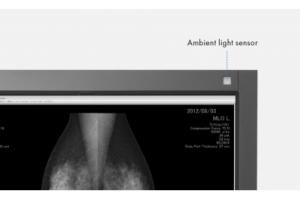

Встроенный фронтальный датчик (IFS), расположенный в передней панели, измеряет яркость и оттенки серого и калибрует его до стандарта DICOM Part 14. Hands-Free IFS выполняет задачи контроля качества и не мешает области просмотра во время использования. Это резко сокращает затраты на рабочую нагрузку и обслуживание, необходимые для поддержания контроля качества монитора.